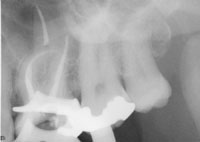

For accuracy purposes, a digital periapical radiograph was taken to confirm the measurements (Figure 3). Notice that although the tooth had four canals, which is highly common for maxillary first molars, files were not placed in all four of them. Placing files in all four canals can sometimes impede a clinician’s ability to accurately visualize where a canal ends. In order to see all four canals it is more effective to take another digital radiograph to get an accurate measurement rather than take several poorly angled views.

Figure 3 Radiograph confirming lengths determined by apex locator.